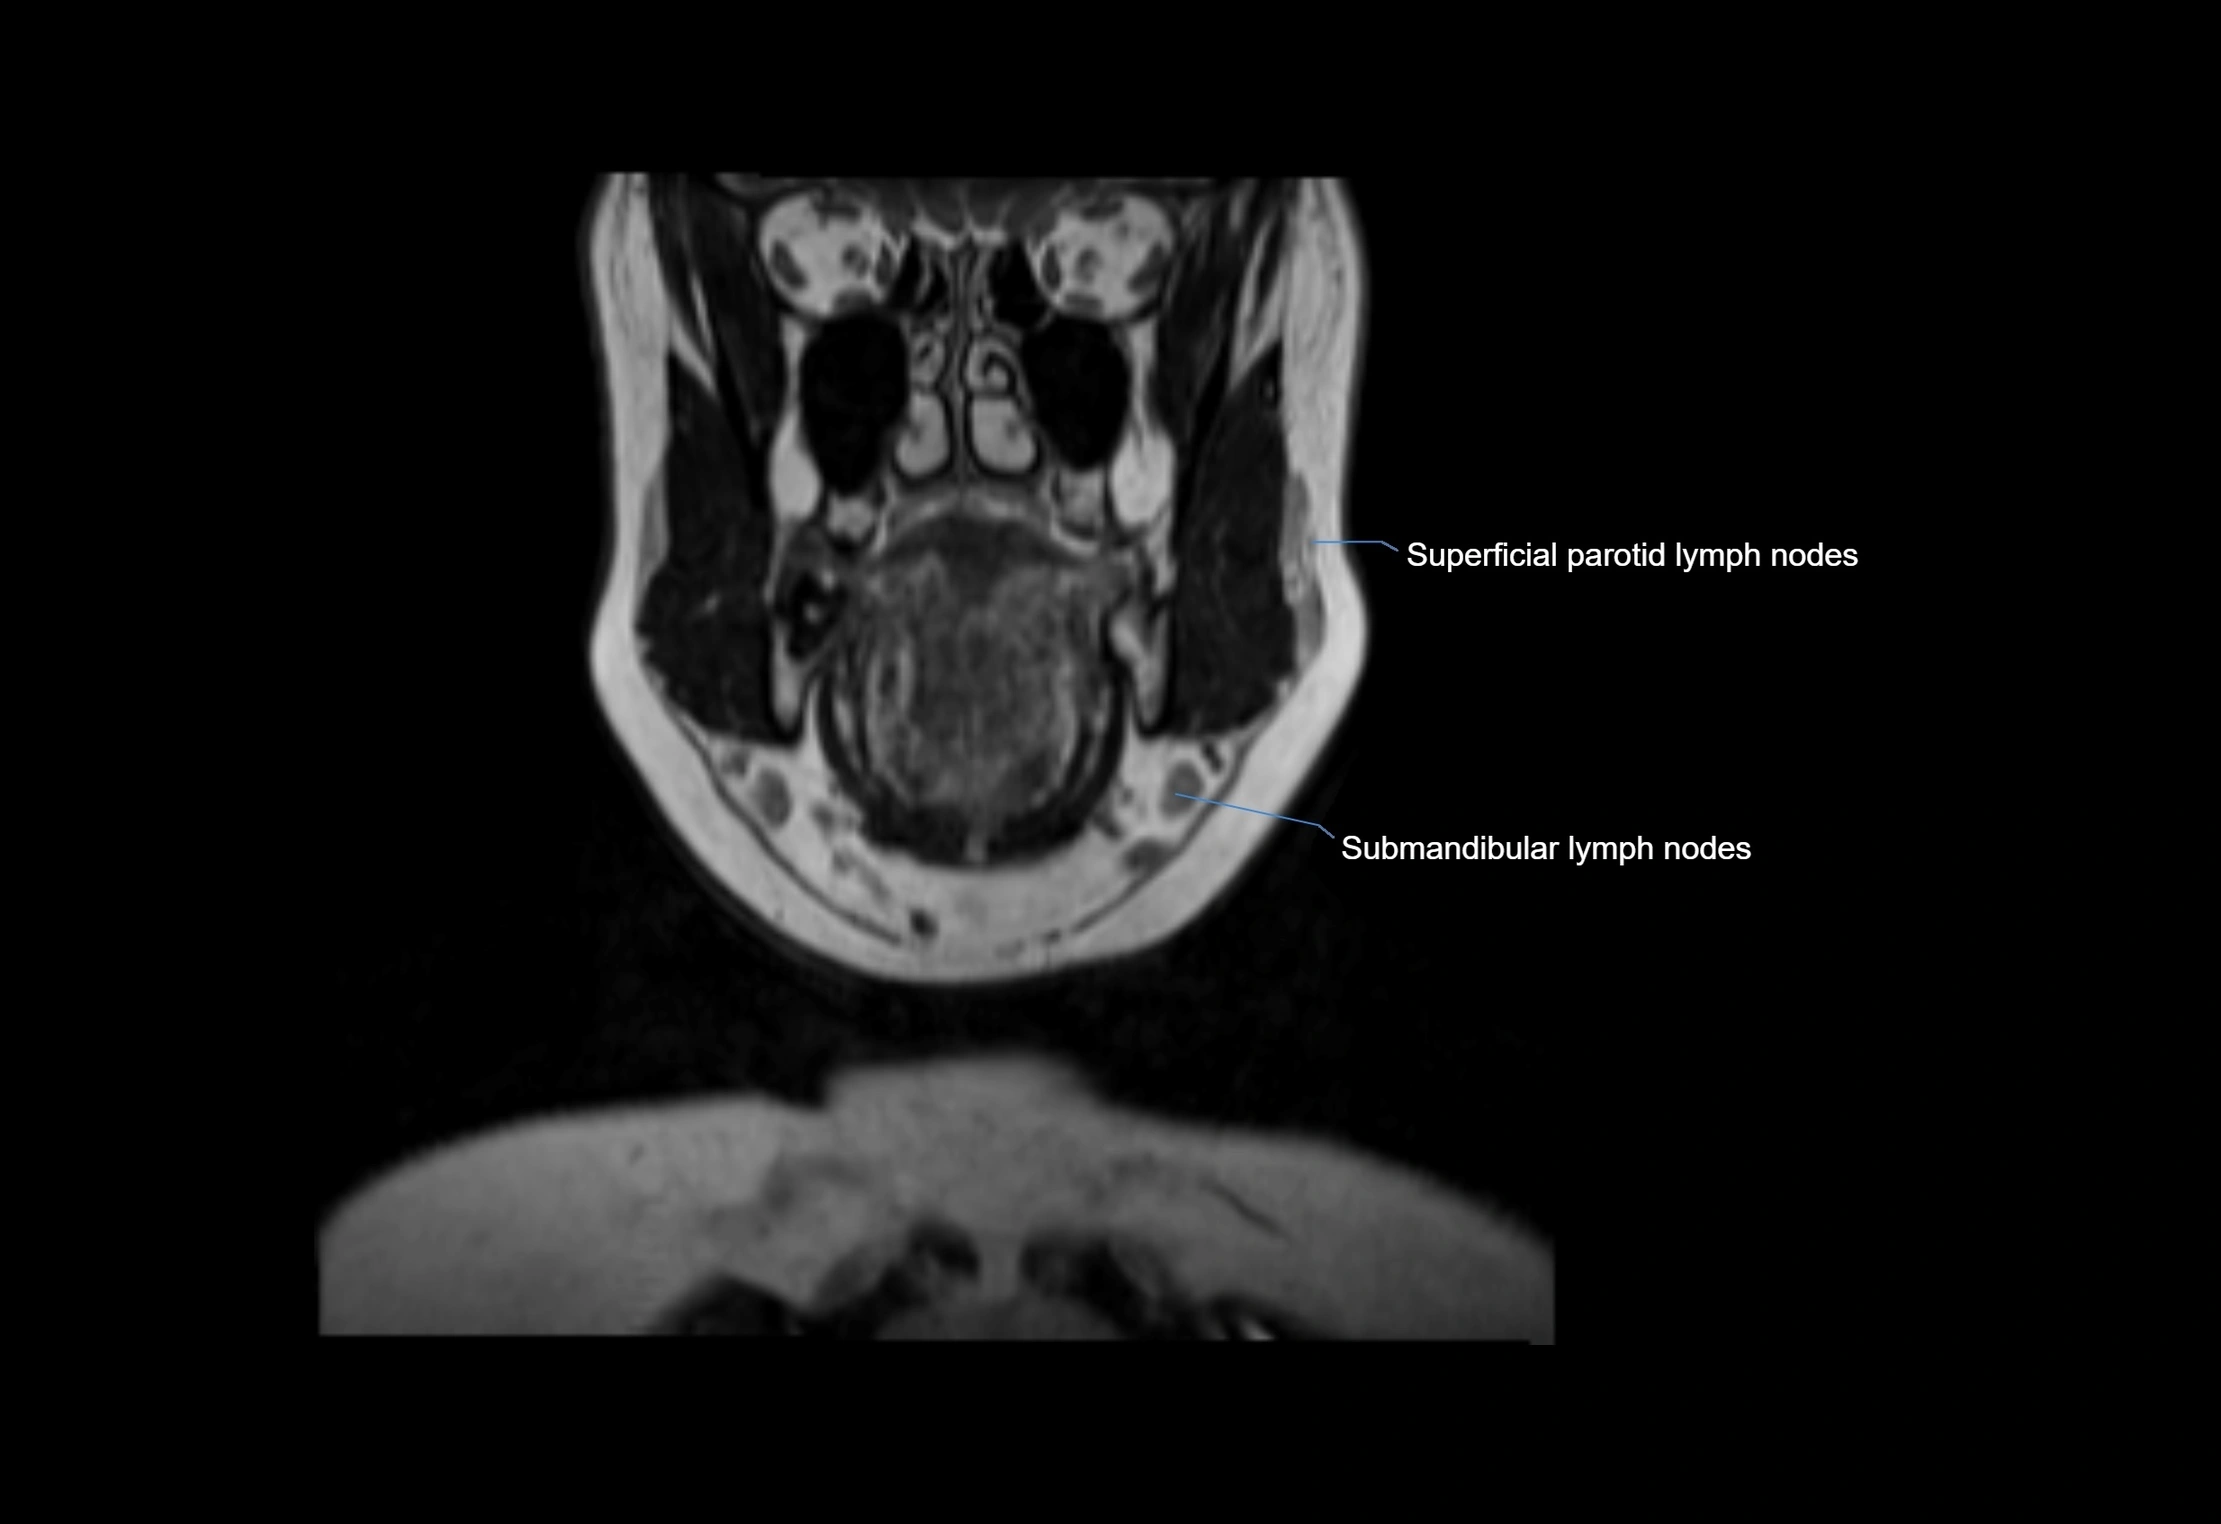

• Found along primary lymph node chains, including preauricular, submandibular, parotid, and occipital regions

MRI Appearance

T1-weighted images:

• Normal accessory nodes appear as small, oval hypointense to intermediate signal structures within subcutaneous fat

• Surrounded by hyperintense fat, enhancing contrast for visualization

T2-weighted images:

• Nodes show intermediate signal, with surrounding fat bright

• Useful for detecting edema, inflammation, or infiltration

• Fatty hilum may appear slightly hyperintense relative to cortex

image